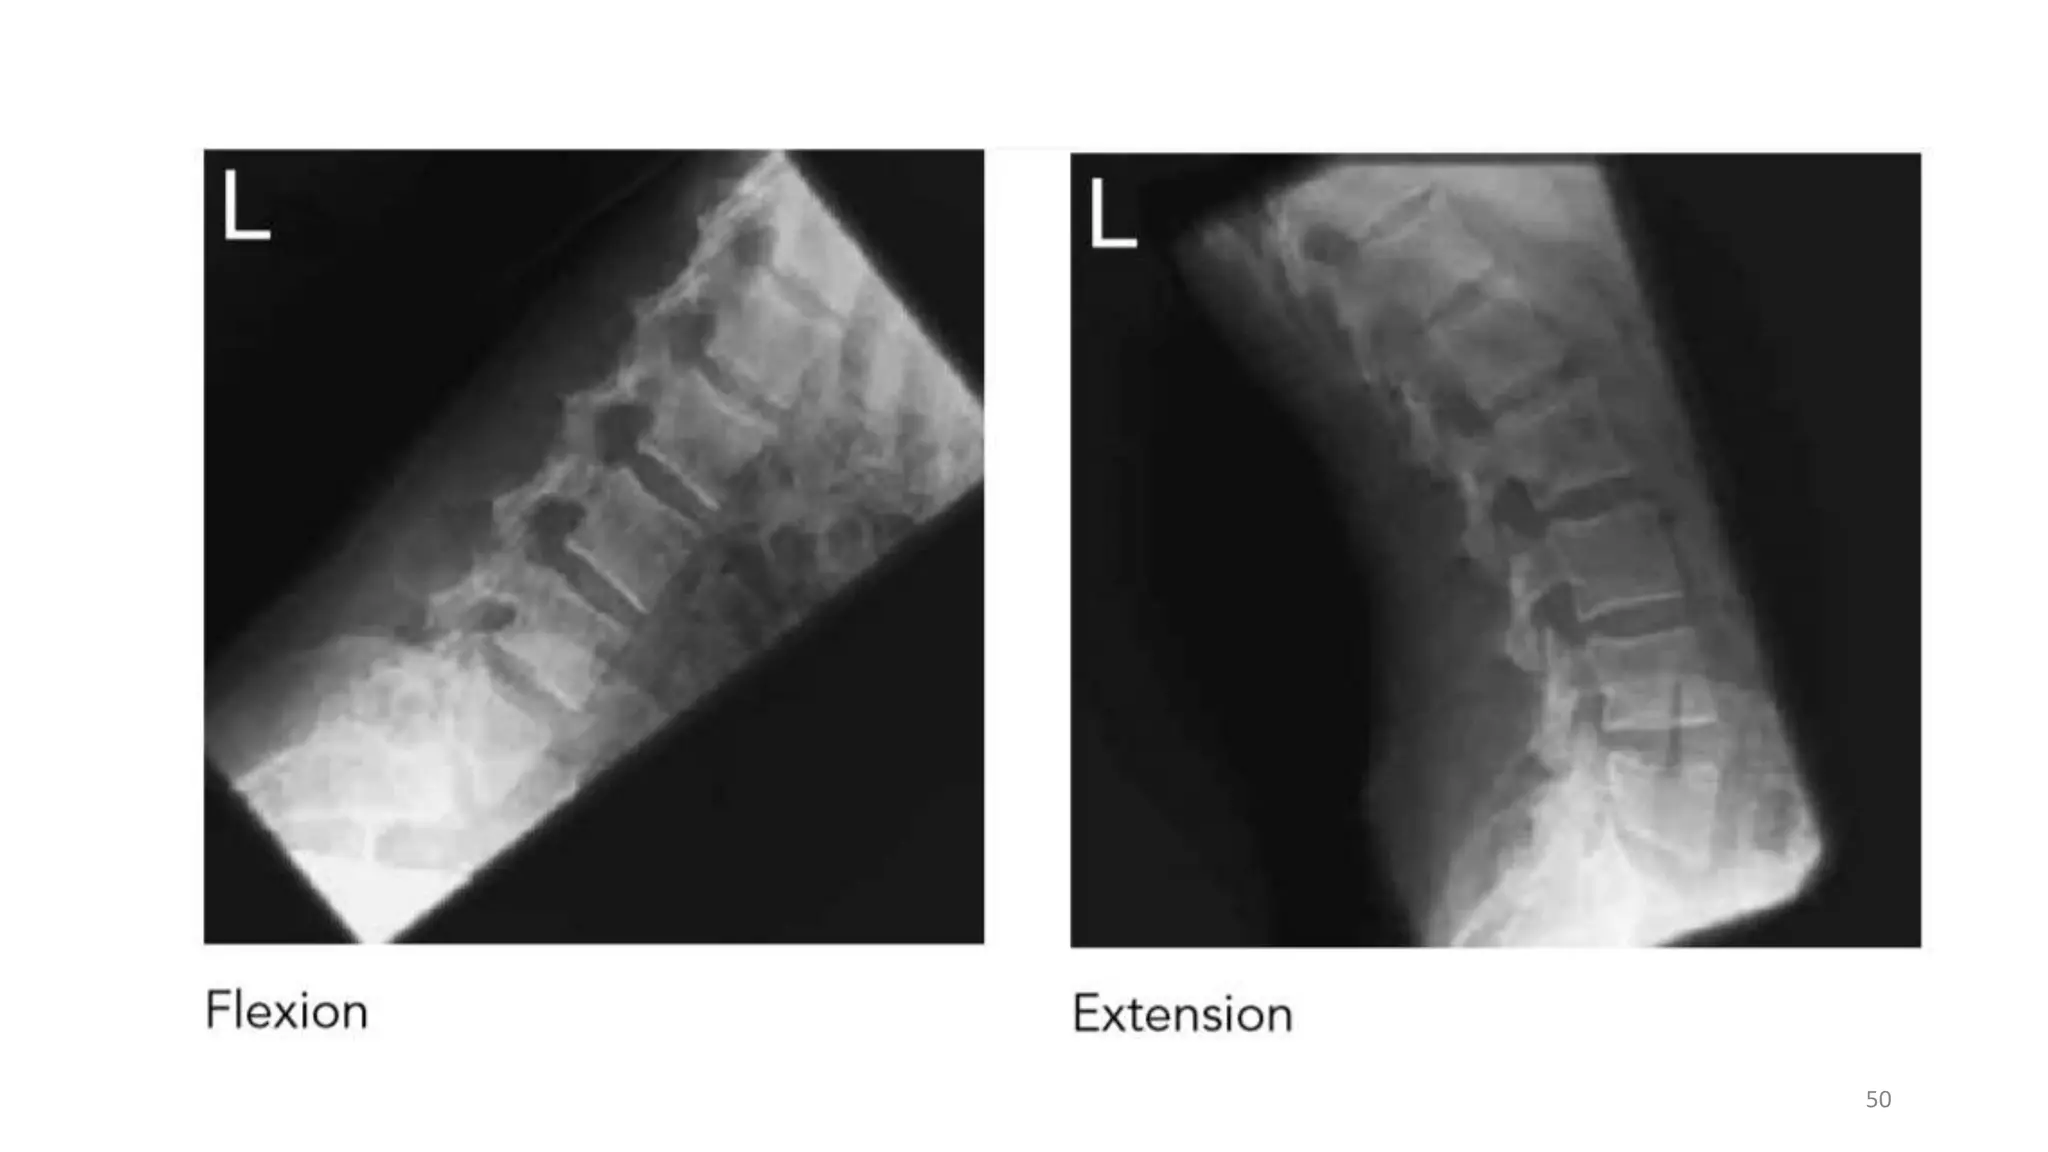

Lateral Flexion and Extension

• Lateral projections in flexion and extension may be requested to

demonstrate mobility and stability of the lumbar vertebrae.

Patient preparation

• This projection may be performed supine, but it is most commonly

performed erect with the patient seated on a stool with either side

against the vertical Bucky.

• A seated position is preferred, since apparent flexion and extension of

the lumbar region is less likely to be due to movement of the hip joints

when using the erect position.

• The dorsal surface of the

trunk should be at right-angles

to the cassette and the

vertebral column parallel to

the cassette.

• For the first exposure the

patient leans forward, For the

second exposure the patient

then leans backward,

• The cassette is centered at

the level of the lower costal

margin, and the exposure is

made on arrested expiration.

Direction and centering of the X-ray beam

• Direct the central ray at right-angles to the

film and towards a point 7.5cm anterior to

the third lumbar spinous process at the level

of the lower costal margin.

Essential image characteristics

• Refer to lateral lumbar spine .

• All of the area of interest must be included

on both projections.